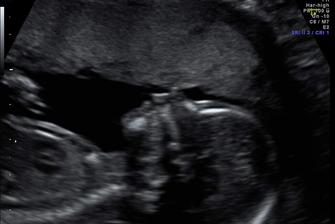

Náš zázrak 2017

Zázrak se snad stane skutečností...